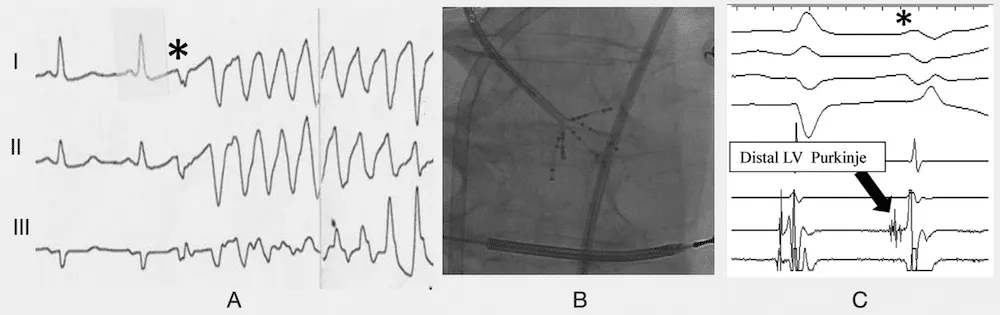

Patterns of Purkinje activity in patients with VF: Haïssaguerre 2019(A) Typical short-coupled ectopy(*) initiating VF.(B) Multielectrode mapping with a multispline catheter recording(C) the earliest activity preceding ectopic beat in the distal left posterior fascicle